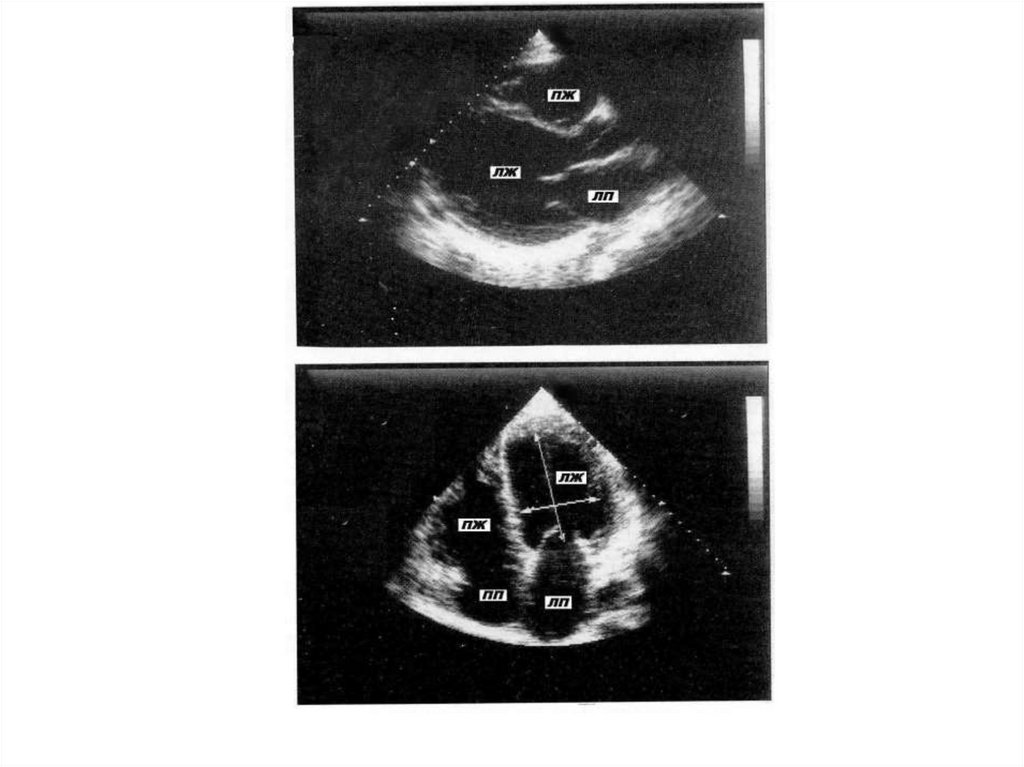

ЭхоКГ критерии ГКМП

Показатель

Диагностический критерий

Толщина передне-перегородочного и

заднего сегментов ЛЖ

≥ 13 мм

Толщина задне-перегородочного и

бокового сегментов ЛЖ

≥ 15 мм

Соотношение толщины МЖП / ЗСЛЖ

> 1,3

Размер левого предсердия

увеличен

Объём полости ЛЖ

нормальный или снижен

Фракция выброса

нормальная или повышена

Диастолическая функция

нарушена

11. ЭхоКГ- признаками обструкции выносящего тракта ЛЖ являются:

• наличие систолического движения вперёд

передней (иногда и задней) створки

митрального клапана и её соприкасание с

МЖП, занимающее иногда до1/3 систолы;

• частичное систолическое прикрытие створок

аортального клапана в момент митральносептального контакта;

• наличие митральной регургитации;

• наличие градиента давления (по данным

допплер-ЭхоКГ).